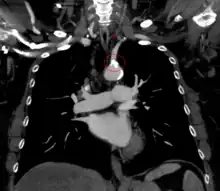

| The proximal part of left subclavian is blocked (shaded artery). This prevents antegrade ("forward") flow to the left arm and left vertebral. As a result, flow in the left vertebral is retrograde ("backwards") towards the left arm. Flow to the brain and circle of Willis is via antegrade right and left carotid and right vertebral arteries. | |